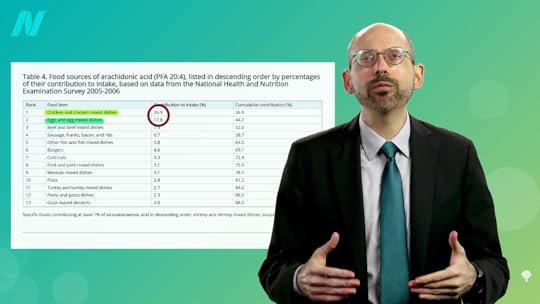

It could be as simple as eicosanoids, the mediators of inflammation that are formed from arachidonic acid. Arachidonic acid is a long-chain, inflammatory, omega-6 fatty acid found in animal fats. As seen below and at 5:04 in my video, the biggest contributors are chicken and eggs, which together contribute nearly half the intake of Americans. That’s also been suggested as an explanation for why those eating more plant-based appear to have better mental health; they aren’t suffering the “cascade of neuroinflammation” caused by arachidonic acid. It’s also why removing eggs, chicken, and other meats was shown to improve mood in a randomized controlled trial, suggesting the arachidonic acid “may negatively impact mood state.” It may also help explain the impact of more plant-based diets on inflammatory diseases like rheumatoid arthritis.